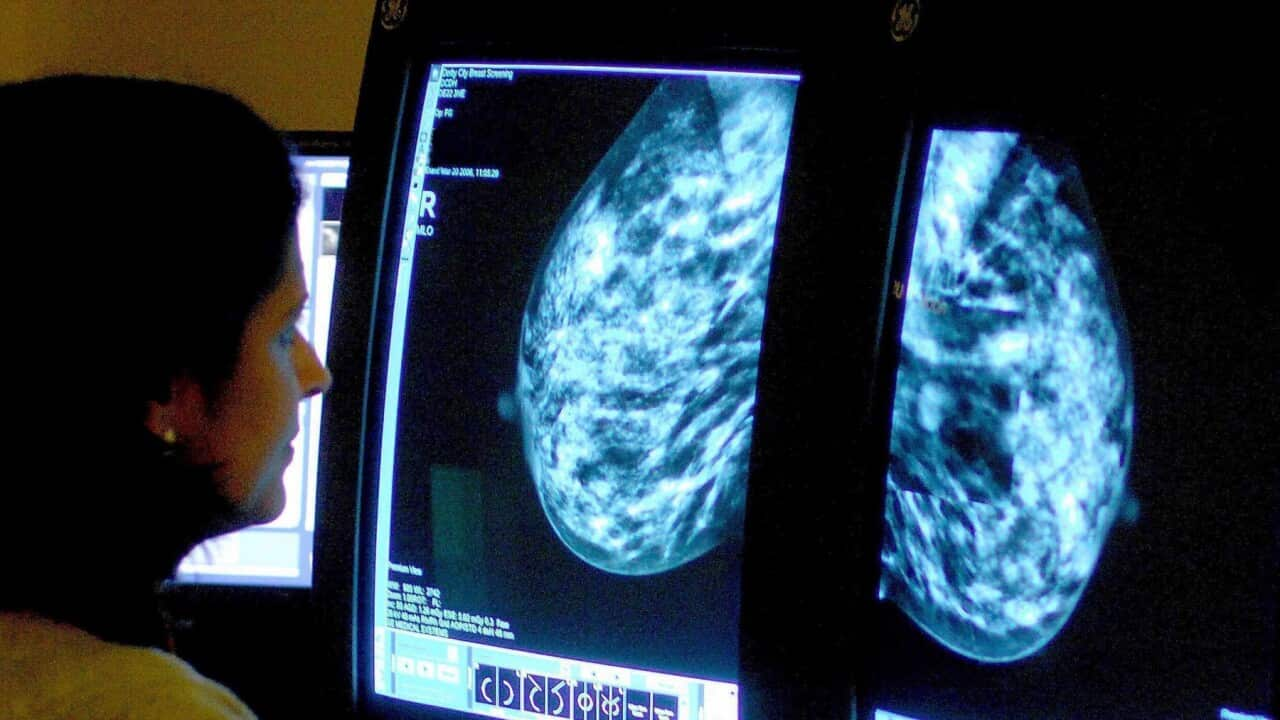

Hôm nay, chúng ta sẽ thực hiện hai bức ảnh về mỗi bên vú, vì vậy chúng ta sẽ bắt đầu với một bức ảnh từ trên xuống và một bức từ mặt bên qua.

Cô Gill Elford đang được một y tá tại bệnh viện thuộc Vương quốc Anh giới thiệu sơ lược về bệnh ung thư vú trước khi tiến hành kiểm tra định kỳ.

Cô là một trong rất nhiều phụ nữ tại Anh trên 50 tuổi phải chịu đựng quá trình kiểm tra có phần khó chịu ba năm một lần.

Còn tại Úc, hiện nay khuyến cáo nên chụp quang tuyến vú hai năm một lần cho những người từ 50 đến 74 tuổi để phát hiện các dấu hiệu sớm.

Nếu việc chụp quang tuyến vú thường bao gồm rất nhiều hình ảnh X-quang về toàn bộ bộ phận này, thì thử nghiệm mới chỉ yêu cầu những người tham gia cung cấp một mẫu nước bọt và tiền sử gia đình của họ.